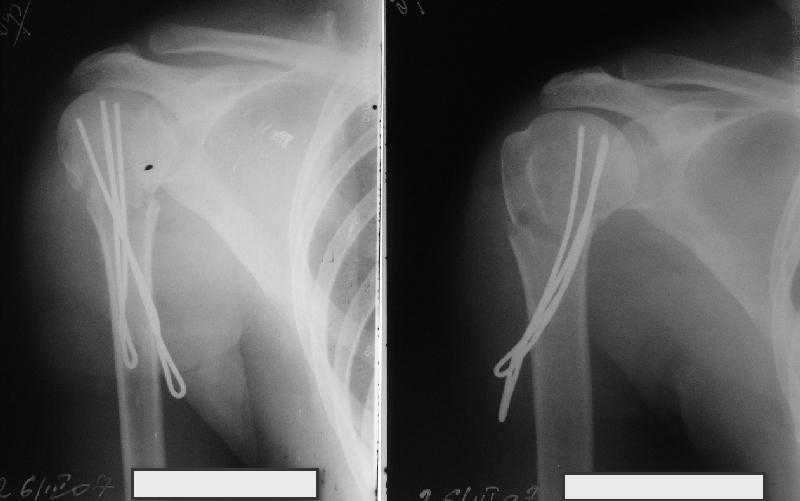

Сделали напряженными спицами по методике А.Ф.Лазарева со товарищи Репозиция сделана спицевым дистрактором, проксимальная спица была проведена в полскости деформации перпендикулярно оси наклонившейся головки. Получилось все довольно легко. Спицы малость покороче можно было сделать, ну да удалять потом легче будет.

Картинка в приложении.